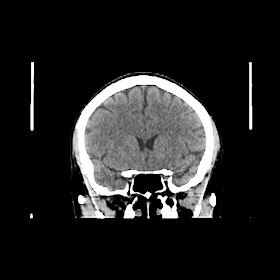

A 50 years old woman with headache, back pain, ghabrahat